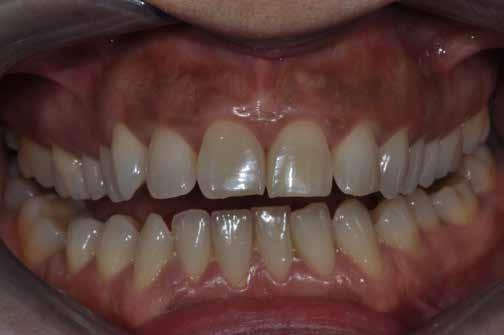

A kezelés során az jelentette a legnagyobb kihívást, hogy a héjakkal ellátott fogak élethűen utánozzák a természetes fogazat megjelenését. A fogpótlás színének, valamint a restaurátumok felszíni textúrájának és alakjának harmonikusan kell a páciens arcesztétikájához és karakteréhez illeszkednie.

A tényleges protetikai ellátás megkezdése előtt a páciens mosolygás közben látható fogait otthoni fogfehérítés keretei között a kérésének megfelelő A1-es fogszín eléréséig fehérítettük. A fehérítés során a későbbiekben héjakkal ellátásra kerülő fogak színén nem változtattunk. A fogak előkészítése részeként csupán a két felső nagymetsző (1.1,2.1) incizális élét kellett kismértékben redukálni. A többi felső front fog (1.3,1.2,2.2,2.3) nem került preparálásra.

nak megfelelően – előkészítjük (orthofoszforsavval történő savazás, lemosás, szárítás és bond réteggel történő fedés). Ezzel egyidejűleg a ragasztásra kerülő héjak is előkészítésre kerülnek (hidrofolysavval történő savazás, lemosás, szárítás, szilanizálás, bond réteggel történő fedés, és végül az alkalmazni kívánt ragasztóanyag felvitele). Ezután a héjakat a fogak felszínén egyesével pozicionáljuk, majd néhány másodpercen keresztül polimerizációs lámpa segítségével megvilágítjuk. Ezt követően a kifolyó ragasztófelesleget eltávolítjuk, majd elvégezzük a restaurátumok végső polimerizálását. A héjak végleges rögzítését követően az esetlegesen visszamaradt ragasztómaradványok eltávolításra kerülnek, valamint ellenőrizzük az okklúzió és artikuláció közben létrejövő fogérintkezéseket. Az optimális esztétikai eredmény biztosítása érdekében kiemelt jelentősége van a papillák helyreállításának (rózsaszín esztétika). A modern fogorvoslás egyik kiemelt célja a fehér- és rózsaszín esztétika közti harmonikus egyensúly megteremtése. A papillák színe, nagysága és szimmetrikus megjelenése meghatározó szerepet tölt be a rózsaszín esztétika kialakításában. Az íny lefutása ugyancsak rendkívül jelentős mértékben befolyásolja a páciens fogazatának esztétikus megjelenését.